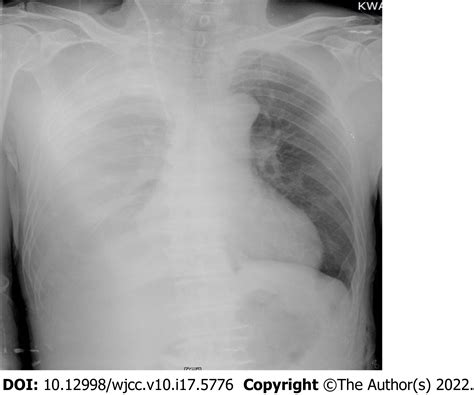

• Pneumothorax: Accidental puncture of the pleural space can lead to a collapsed lung.

• Hemothorax: Injury to the surrounding vessels can result in bleeding into the pleural space.